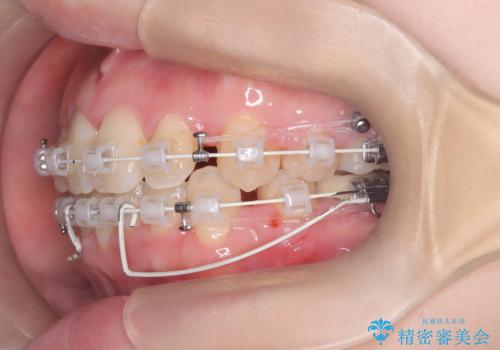

- 「歯のデコボコ、八重歯、口ボコが気になる」を主訴に来院された患者様です。

上下左右4番(4本)の歯を抜歯しワイヤー矯正で治療を行いました。

計4本の抜歯を行い、歯のデコボコと口元がすっきりし、大変ご満足していただけました。